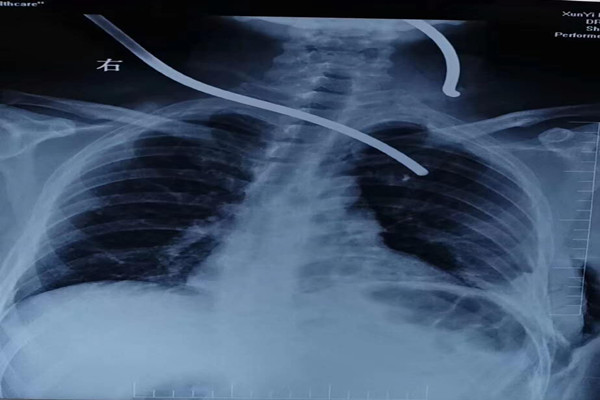

“伤情刻不容缓!病人必须马上送进手术室实施急救手术!”,郭医生果断遵从生命第一的急救原则,一边打电话向薛锋主任报告,一边与手麻科医生联系。胸外科薛锋主任第一时间赶到科室,在了解伤情后迅速做出判断,“患者为钢筋颈、胸部贯通伤,一根从左背部刺入胸腔,一根为左颈部贯通伤,伤情危急,需立即急诊手术抢救”。随后,绿色通道启动,胸外科及手麻科成立手术及麻醉团队,做好心脏及大血管损伤的手术准备,迅速完成双腔气管插管麻醉,建立中心静脉通道及动脉血压监测通路,做好自体血液回收准备。

各项术前准备工作极速完成后,由胸外科薛锋主任带领的手术组、王海燕主任医师带领的麻醉组在手术台前进行了细致高效的讨论,迅速达成手术预案。在自体血液回收及库血到位的保障下,手术有条不紊的展开。术中,薛锋主任迅速进行胸腔探查,清除胸腔积血后探明伤情:患者左侧多发肋骨骨折、左侧创伤性血气胸、左肺下叶贯通伤、钢筋紧贴着心脏及胸主动脉等重要脏器,颈部钢筋紧贴颈总动脉。在确保避免二次损伤的情况下缓慢拔出钢筋,伤口污染严重,仔细进行伤口清创后完成止血及肺修补术。经过约4个多小时的不懈努力,钢筋顺利取出,各破裂伤口修补完成,生命体征维持平稳,术后病人顺利返回ICU监护治疗。